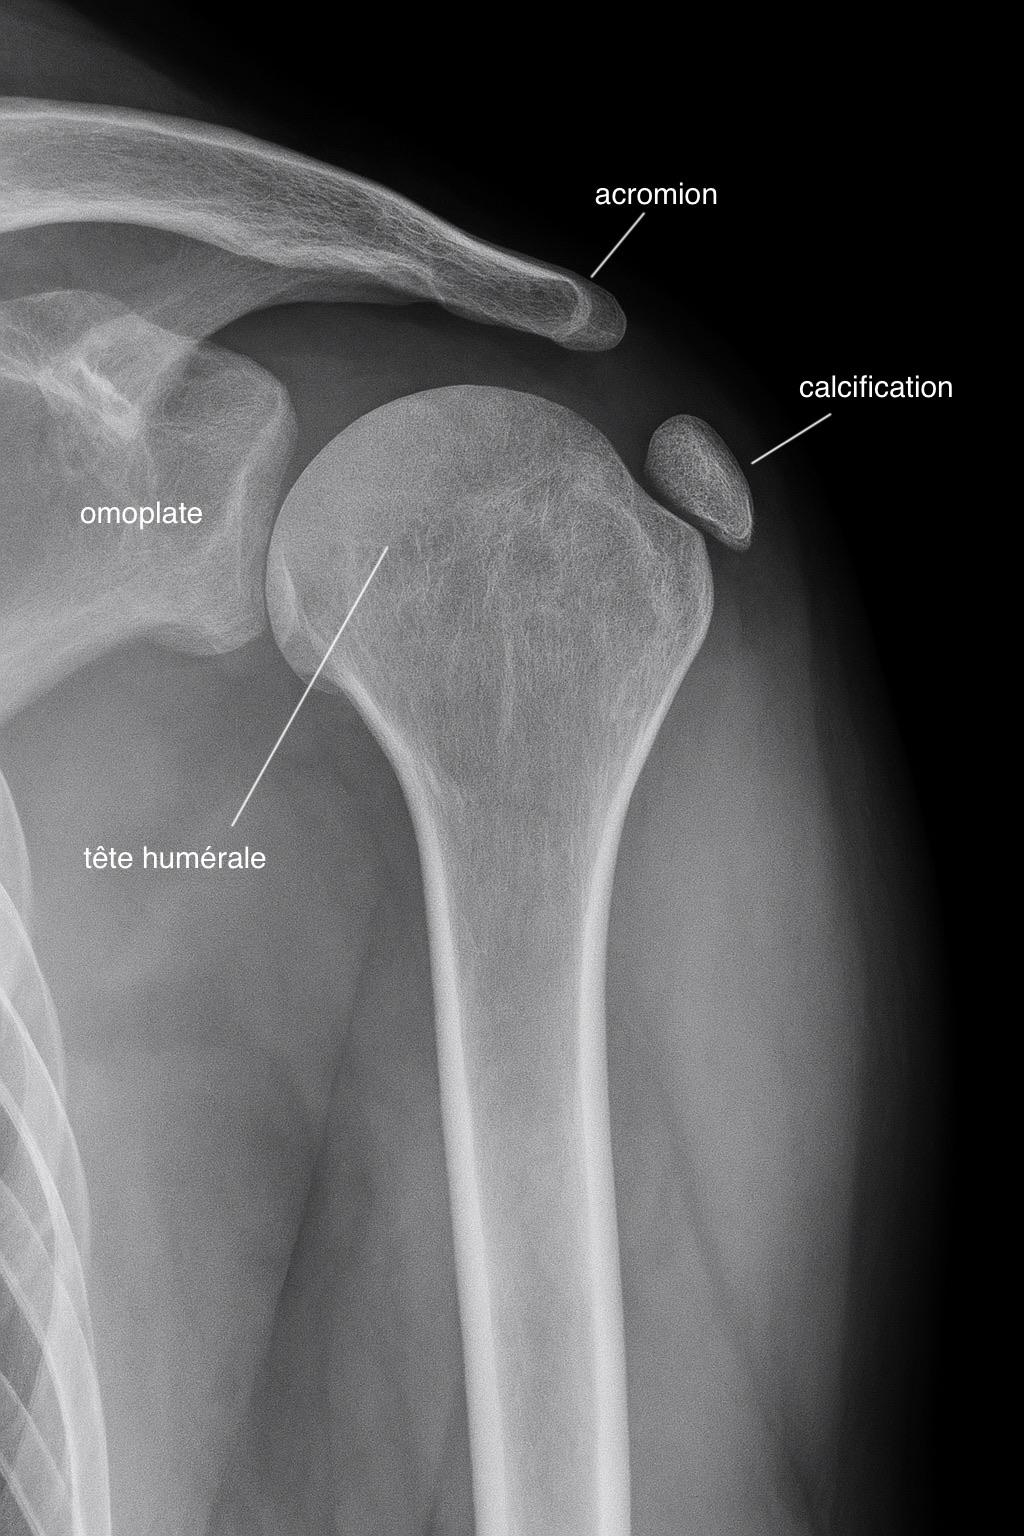

Anatomie des calcifications de l'épaule - Illustration médicale détaillée

Dépôts calciques dans les tendons de la coiffe des rotateurs

Les calcifications de l'épaule correspondent à des dépôts de calcium au sein des tendons, le plus souvent le supra-épineux. Ces dépôts sont responsables de douleurs aiguës et de limitations fonctionnelles importantes.

Examens d'imagerie

Radiographies

Examen de référence pour visualiser les calcifications et évaluer leur taille et localisation